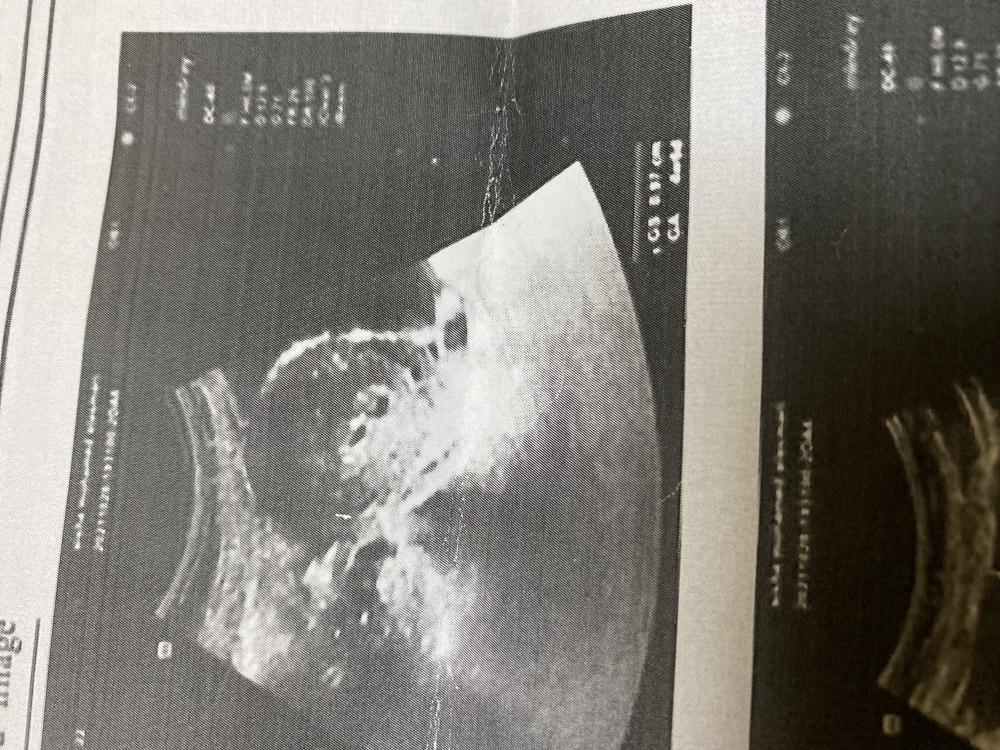

بنات شوفوا سوناري خمس اسابيع ويومين تؤام او ايش النقطتين هذي؟

السلام عليكم ورحمة الله بنات شوفوا سوناري خمس اسابيع ويومين تؤام او ايش النقطتين هذي؟

يااااارب الله يرزقك انا اشوف تووم وش قالت الدكتورره